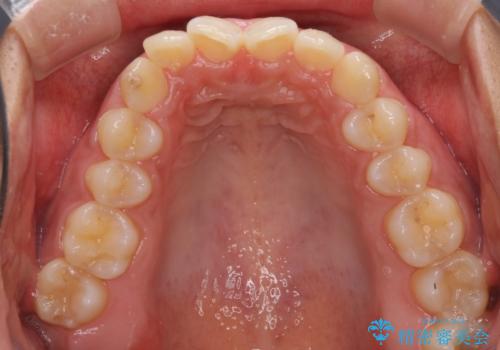

- 深い咬み合わせ(ディープバイト)と前歯のデコボコを気にして来院された患者様です。

インビザラインによる上下歯列の側方拡大と後方移動、IPR(歯と歯の間を削る)にるスペースの獲得により、デコボコとディープバイトを改善することとしました。

1日22時間の装着時間をしっかり守ってくださったので、予定通り1年で治療を終えることができました。

ディープバイトによる食いしばり癖も解消され、患者様には大変満足していただきました。